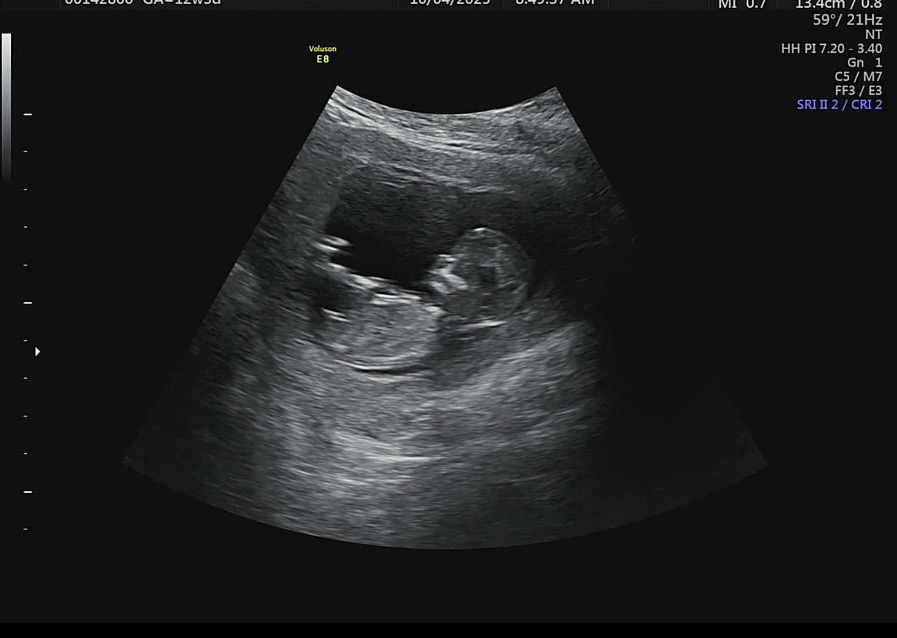

안녕하세요 !!! 12주 3일차 초음차사진입니다 ㅎㅎ 아들일까요 딸일까요 ?????